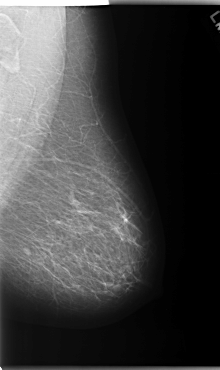

C_0174_1.RIGHT_CC

RIGHT_CC LINES 5912 PIXELS_PER_LINE 3672 BITS_PER_PIXEL 12 RESOLUTION 50 OVERLAY

FILE: C_0174_1.RIGHT_CC.OVERLAY

TOTAL_ABNORMALITIES 3

ABNORMALITY 1

LESION_TYPE MASS SHAPE OVAL MARGINS CIRCUMSCRIBED

ASSESSMENT 4

SUBTLETY 5

PATHOLOGY BENIGN

ABNORMALITY 2

LESION_TYPE MASS SHAPE OVAL MARGINS MICROLOBULATED

PATHOLOGY MALIGNANT

ABNORMALITY 3